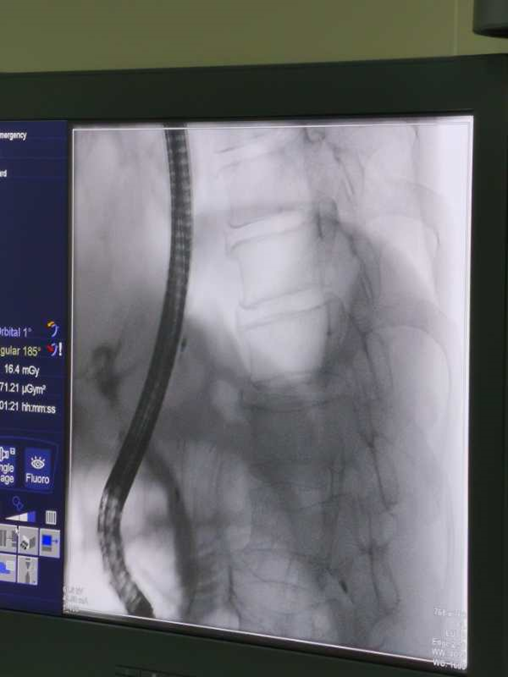

术中所见

造影→乳头切开→网篮取石→鼻胆管引流

取石篮是什么小小结石  “胆”敢来犯——记平湖二院又一例ERCP微创胆道取石术_https://www.jmylbn.com_新闻资讯_第2张